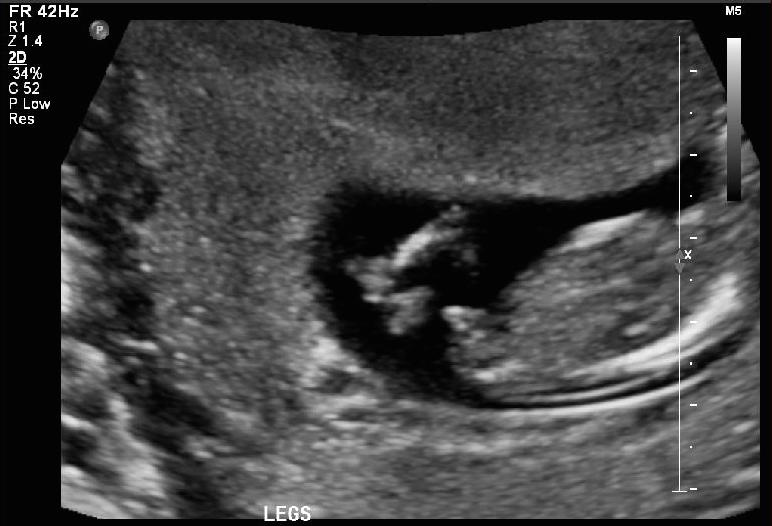

I had my anatomy scan done today. I am 12w4days. I ll get my harmony results in a day or two. Can anyone please guess?

Attachment 38072

Giving a slight boy lean. Some pics show stacking, and some show an angled nub. 🤞🏻for you!

Boy lean but not super confidant as baby is a bit twisted. Good luck, I hope this is your little man :happy:

Thank you Nicoler. Yes, my tech was saying baby is moving too much all the time. She tried to take potty shot too but baby's legs was crossed.